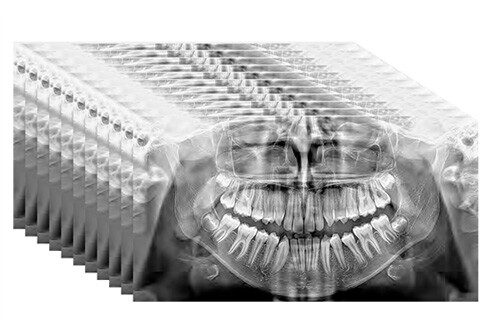

MULTIPAN SuperHD jusqu’à 11 couches

La technologie DCIII innovante - qui optimise la profondeur de foyer et augmente le niveau de contraste et, en conséquence, le pouvoir de résolution réel - permet d’obtenir un panoramique SuperHD à partir d’un ensemble de données extrêmement vaste, pour obtenir un MultiPAN à 11 couches. Particulièrement utile en cas de morphologies complexes.